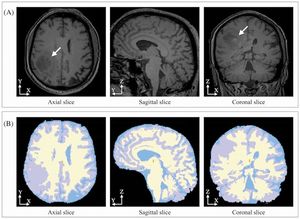

MRI-Only Based Radiotherapy Treatment Planning for the Rat Brain on a Small Animal Radiation Research Platform (SARRP)

Publication: PLoS One. 2015 Dec 3;10(12):e0143821. PMID: 26633302 | PDF Authors: Gutierrez S, Descamps B, Vanhove C. Institution: Medical Image and Signal Processing Group, Ghent University-iMinds Medical IT department, Ghent, Belgium. Background/Purpose: Computed tomography (CT) is the standard imaging modality in radiation therapy treatment planning (RTP). However, magnetic resonance (MR) imaging provides superior soft tissue contrast, increasing the precision of target volume selection. We present MR-only based RTP for a rat brain on a small animal radiation research platform (SARRP) using probabilistic voxel classification with multiple MR sequences. Six rat heads were imaged, each with one CT and five MR sequences. The MR sequences were: T1-weighted, T2-weighted, zero-echo time (ZTE), and two ultra-short echo time sequences with 20 μs (UTE1) and 2 ms (UTE2) echo times. CT data were manually segmented into air, soft tissue, and bone to obtain the RTP reference. Bias field corrected MR images were automatically segmented into the same tissue classes using a fuzzy c-means segmentation algorithm with multiple images as input. Similarities between segmented CT and automatic segmented MR (ASMR) images were evaluated using Dice coefficient. Three ASMR images with high similarity index were used for further RTP. Three beam arrangements were investigated. Dose distributions were compared by analysing dose volume histograms. The highest Dice coefficients were obtained for the ZTE-UTE2 combination and for the T1-UTE1-T2 combination when ZTE was unavailable. Both combinations, along with UTE1-UTE2, often used to generate ASMR images, were used for further RTP. Using 1 beam, MR based RTP underestimated the dose to be delivered to the target (range: 1.4%-7.6%). When more complex beam configurations were used, the calculated dose using the ZTE-UTE2 combination was the most accurate, with 0.7% deviation from CT, compared to 0.8% for T1-UTE1-T2 and 1.7% for UTE1-UTE2. The presented MR-only based workflow for RTP on a SARRP enables both accurate organ delineation and dose calculations using multiple MR sequences. This method can be useful in longitudinal studies where CT's cumulative radiation dose might contribute to the total dose. |

Illustration of a CB-CT and five MR images of the same animal. a) Coronal CB-CT image and (b)-(f) biased field corrected and masked coronal MR images using a T1-weighted (b), T2-weighted (c), ZTE (d), UTE1 (e) and UTE2 (f) sequence. All CB-CT images were first co-registered using 3D Slicer version 3.6.3 by rigid body transformations using normalized mutual information. |